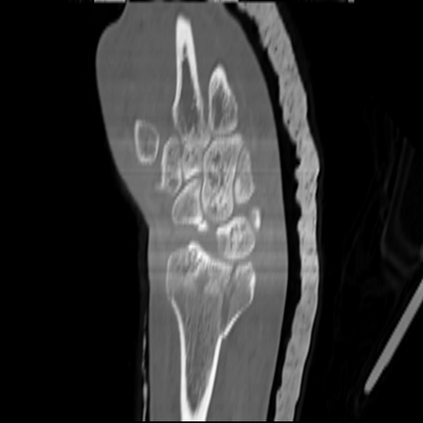

CT reconstruction provides radiologists with images for diagnosis and treatment, yet current deep learning methods are typically limited to specific anatomies and datasets, hindering generalization ability to unseen anatomies and lesions. To address this, we introduce the Multi-Organ medical image REconstruction (MORE) dataset, comprising CT scans across 9 diverse anatomies with 15 lesion types. This dataset serves two key purposes: (1) enabling robust training of deep learning models on extensive, heterogeneous data, and (2) facilitating rigorous evaluation of model generalization for CT reconstruction. We further establish a strong baseline solution that outperforms prior approaches under these challenging conditions. Our results demonstrate that: (1) a comprehensive dataset helps improve the generalization capability of models, and (2) optimization-based methods offer enhanced robustness for unseen anatomies. The MORE dataset is freely accessible under CC-BY-NC 4.0 at our project page https://more-med.github.io/